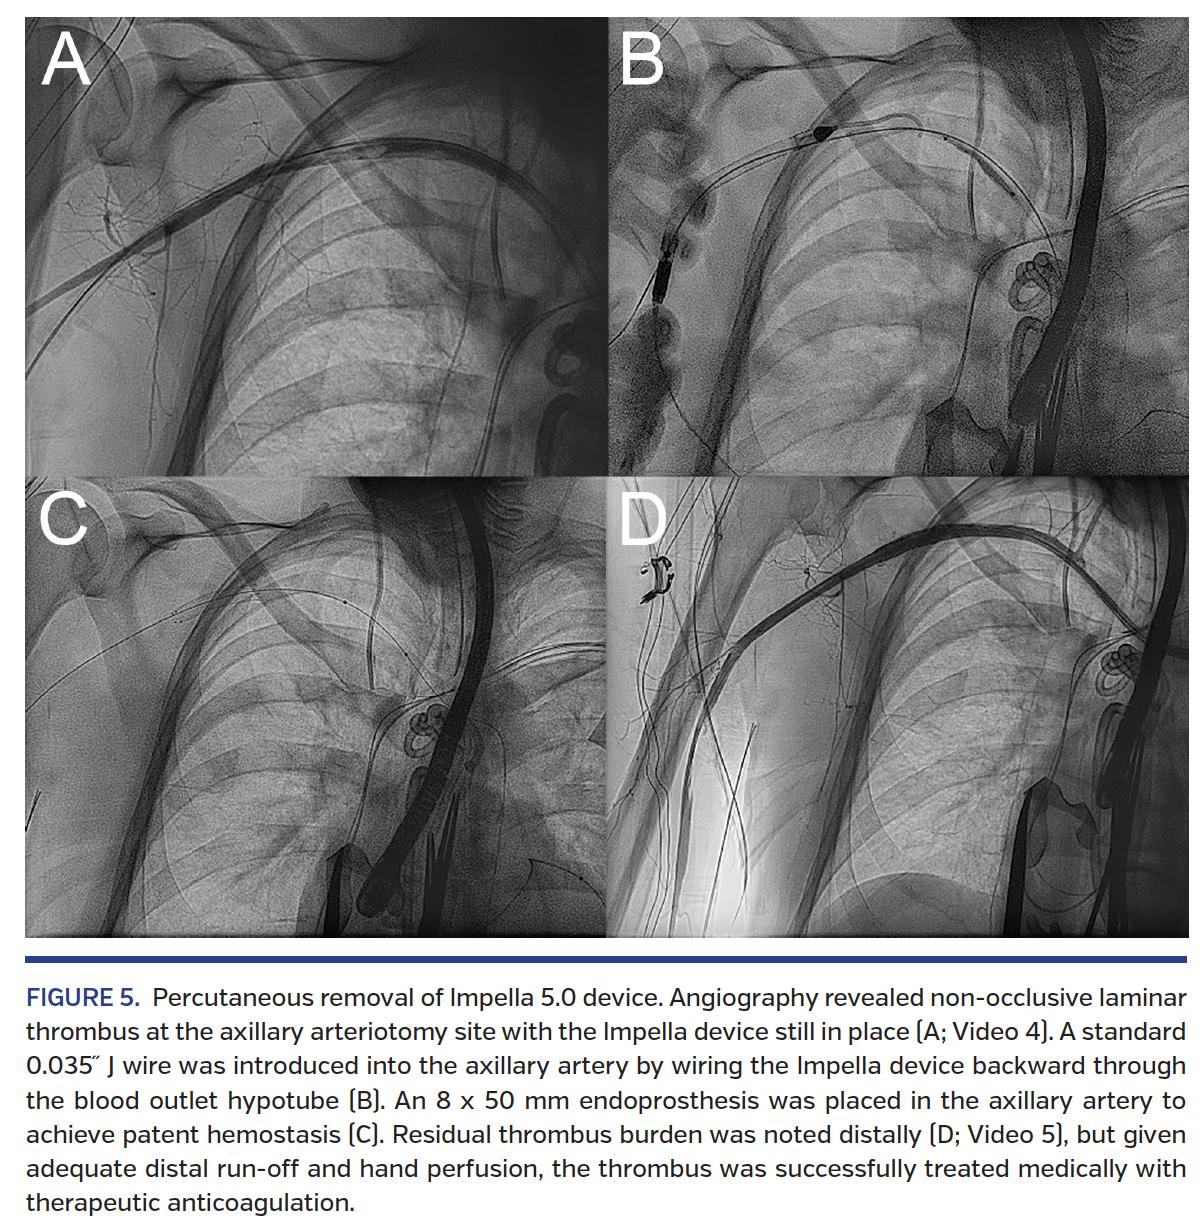

On Impella day 17, the patient underwent durable LVAD placement in the hybrid operating room with coordinated percutaneous removal and closure of the Impella device. Not unexpectedly, angiography at the time of removal revealed non-occlusive laminar thrombus at the axillary arteriotomy site with patent distal flow (Figure 5A, Video 4). For distal embolic protection, a 4 mm FilterWire EZ embolic protection system (Boston Scientific) was positioned in the proximal brachial artery via 6 Fr right femoral access. To assist in hemostasis, an 8 x 20 mm Admiral Xtreme percutaneous transluminal angioplasty balloon was positioned proximal to the axillary arteriotomy site over the FilterWire. Wire access into the axillary artery across the arteriotomy was reestablished by pulling the Impella back such that the outflow cage was externalized but the inflow cage remained in the axillary artery. A standard 0.035˝ J-wire was introduced into the artery by wiring the Impella device backward through the blood outlet hypotube (Figure 5B). Bleeding was minimized during this time by inflating the proximal Admiral balloon to 2 atm and providing proximal manual pressure. The Impella 5.0 device was then completely withdrawn with firm traction. Suture-mediated closure was attempted with deployment of three Perclose vascular closure devices, but residual bleeding was noted. Facilitated hemostasis with a 3 minute inflation of the Admiral balloon across the arteriotomy was attempted without success, at which time an 8 x 50 mm Viabahn endoprosthesis (W. L. Gore & Associates, Inc) was successfully deployed in the axillary artery to achieve patent hemostasis (Figure 5C). During this process, the non-occlusive laminar thrombus migrated distally to the axillary artery, where it was noted to be occlusive. This was treated with retrieval using the FilterWire, and aspiration thrombectomy using an 8 Fr, 90 cm Pinnacle Destination guiding sheath (Terumo Interventional Systems). Angioplasty using a 6 x 150 mm Sterling balloon (Boston Scientific) was also performed in the brachial and axillary arteries. Angiography demonstrated residual non-occlusive thrombus in the brachial artery, but adequate distal run-off (Figure 5D, Video 5) confirmed by radial artery duplex ultrasound. The residual thrombus was treated with therapeutic anticoagulation, which was also indicated for the LVAD. Arterial duplex ultrasound of the right upper extremity 5 days after removal revealed pulsatility without evidence of significant stenosis in the brachial and antegrade flow into all digits.